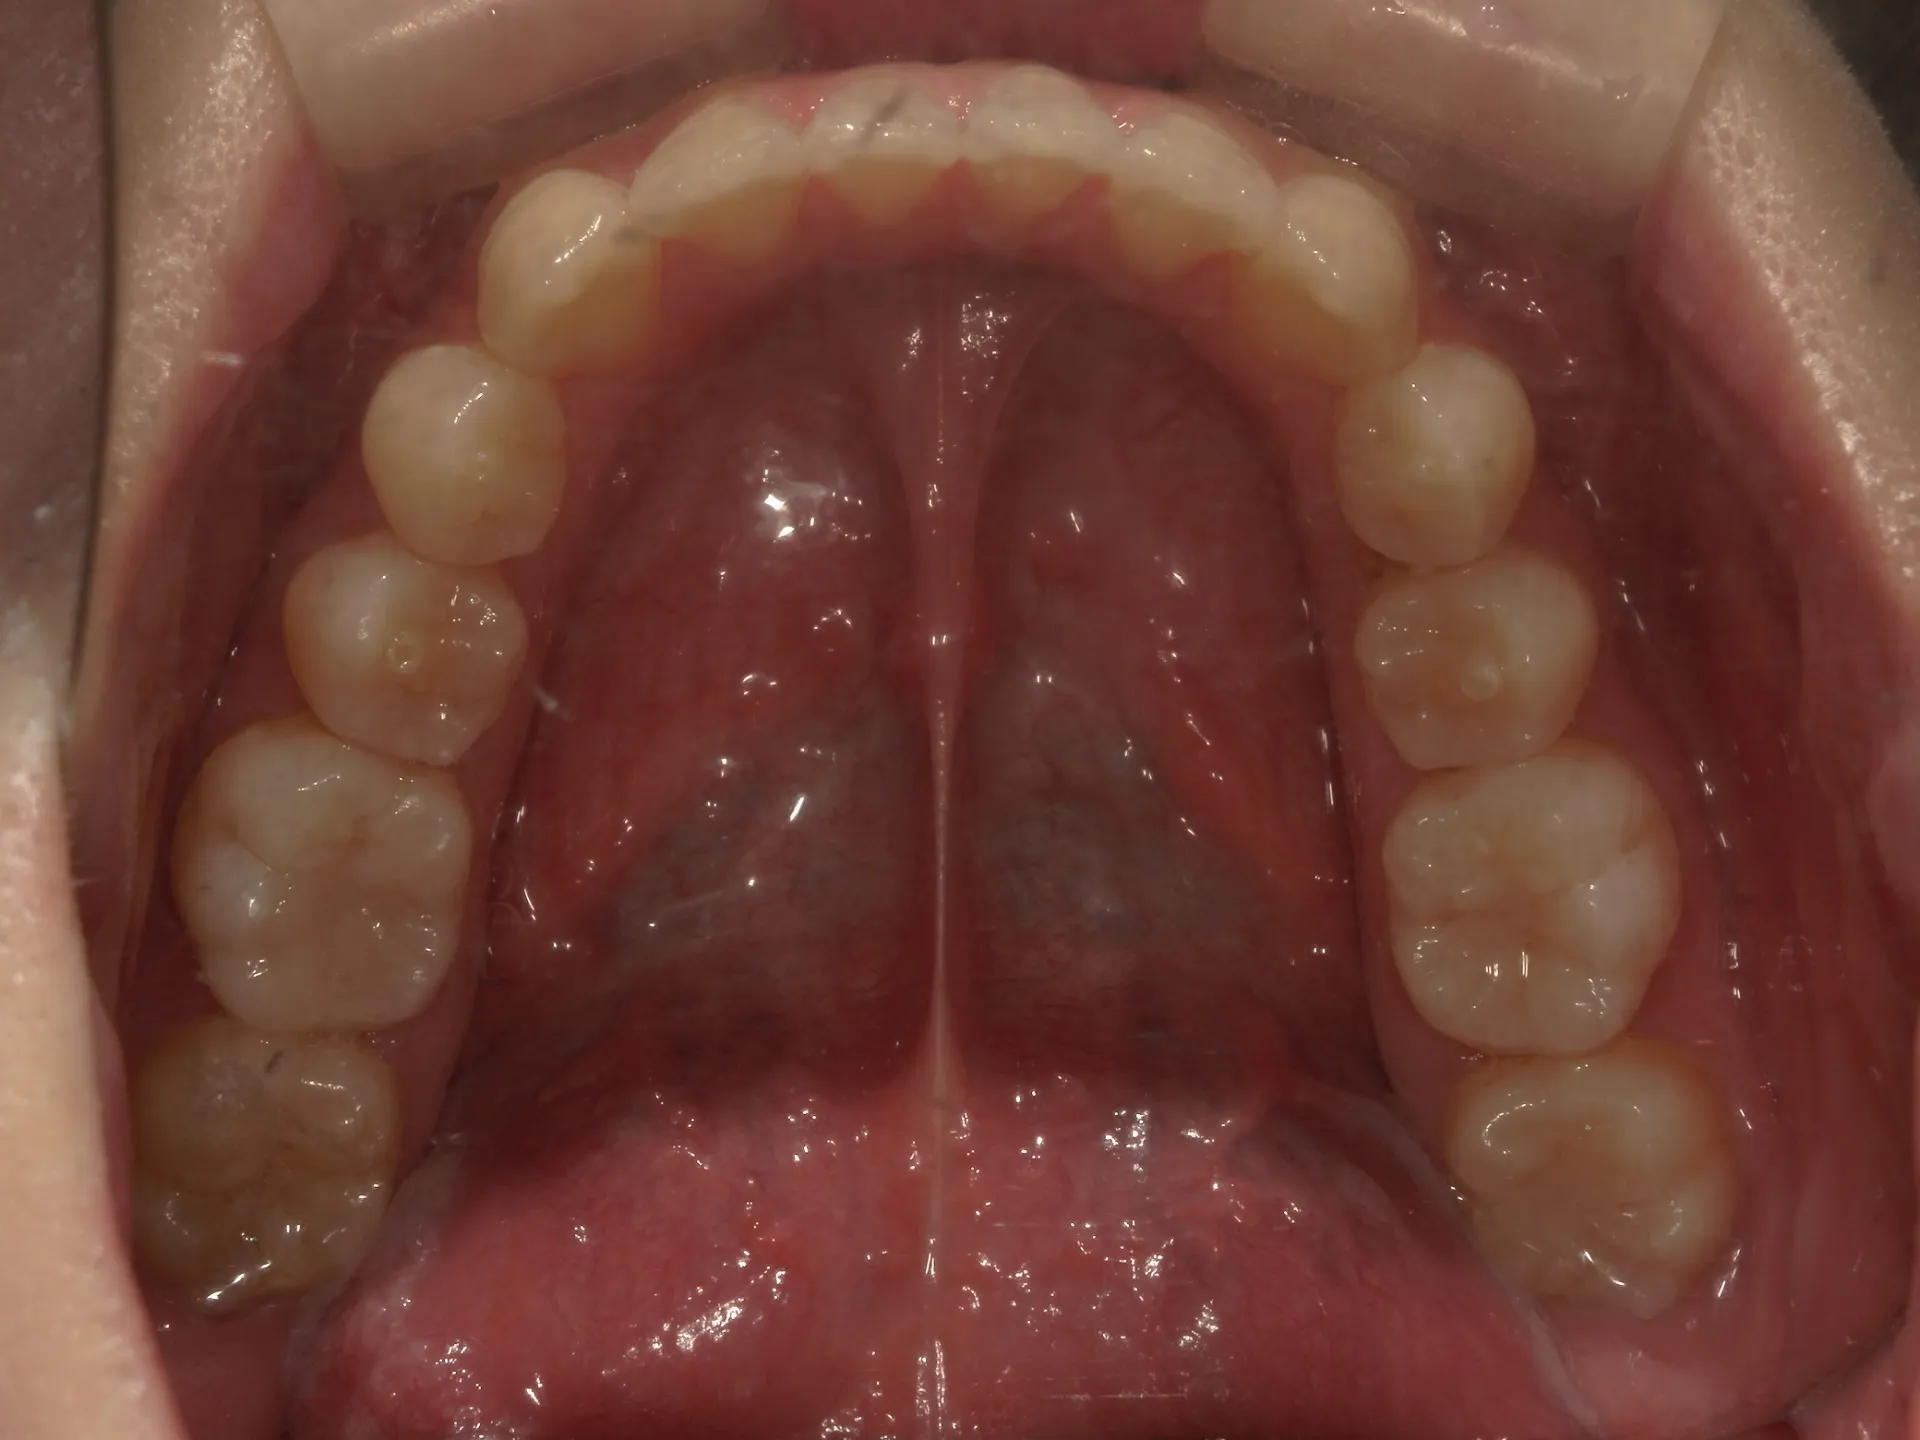

今回はマウスピース矯正で治療した八重歯の矯正についてご紹介いたします。

どこまでが軽度でどこまでが中等度のガタツキなのかにもよりますが、治療前の歯並びであれば患者さんの協力も当然必要ですが、マウスピース矯正でも十分治療できることが分かります。